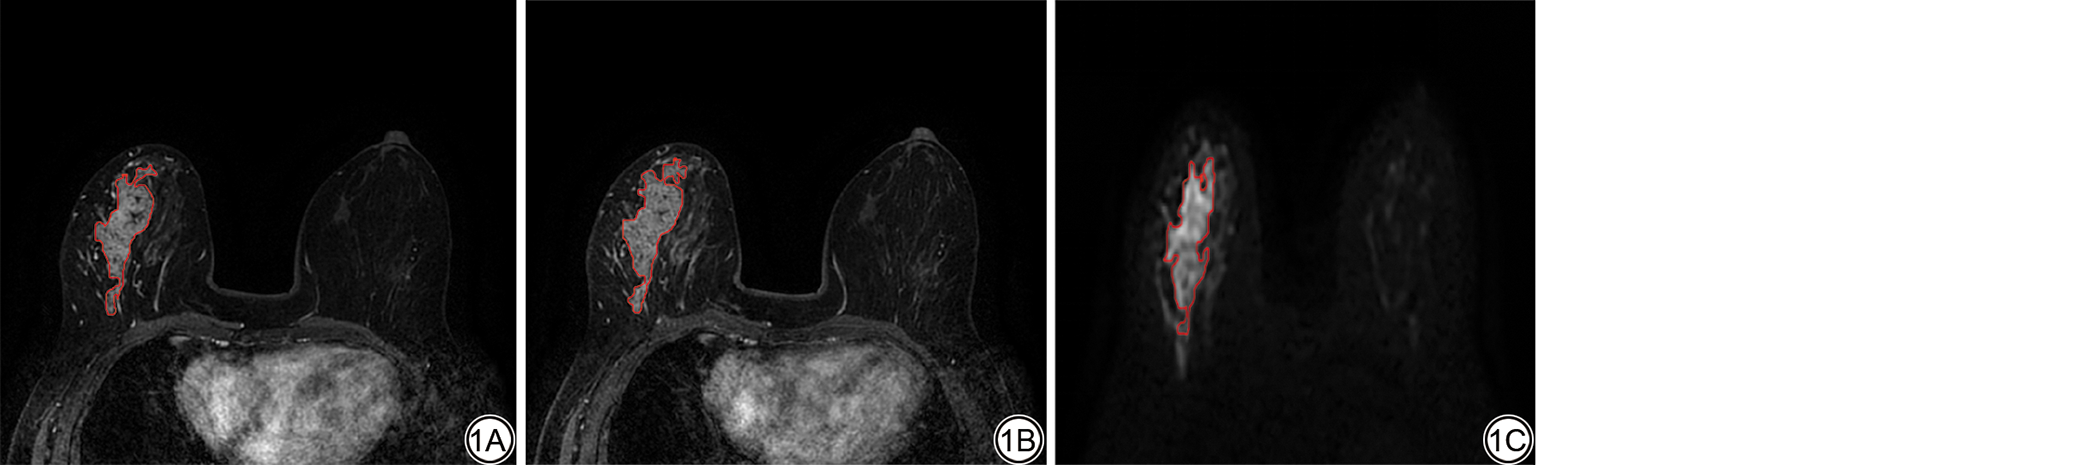

使用ITK-SNAP软件,首先导入患者的DCE-2期、DCE-8期及DWI图像,以DCE-2期图像为固定基准序列,采用刚性配准算法将DCE-8期与DWI图像与之进行空间对齐;同时放射科医师通过肉眼观察解剖结构对应关系进行手动校正,进一步确保各序列间空间位置的精准匹配。配准校正后,一名住院医师(3年乳腺诊断经验)和另一名主治医师(5年乳腺诊断经验)分别独立对肿瘤区域进行手动逐层勾画。若两人勾画的ROI存在不一致,则与1名具有10年乳腺影像诊断经验的副主任医师进行商讨,若商讨结果仍不一致,则与另1名具有20年乳腺影像诊断经验的主任医师协商以确定肿瘤边界,并生成肿瘤三维感兴趣区(volume of interest, VOI)(图1)。随后,使用基于Python(3.7.6)的FeAture Explorer(FAE)软件提取影像组学特征,提取的特征类型包括一阶统计特征值、形状特征、灰度共生矩阵等纹理特征以及经过小波变换得到的特征。

图1  ROI的勾画。女,51岁,非肿块强化型乳腺癌患者。1A:增强早期(DCE-2);1B:增强延迟期(DCE-8);1C:扩散加权成像。红色曲线为病灶ROI。DCE:动态对比增强;ROI:感兴趣区。

Fig. 1  ROI delineation of the region of interest. Female, 51 years old, patient with non-mass enhancement breast cancer. 1A: Early enhancement phase (DCE-2); 1B: Delayed enhancement phase (DCE-8); 1C: Diffusion-weighted imaging. Red curve indicates the lesion ROI. DCE: dynamic contrast-enhanced; ROI: region of interest